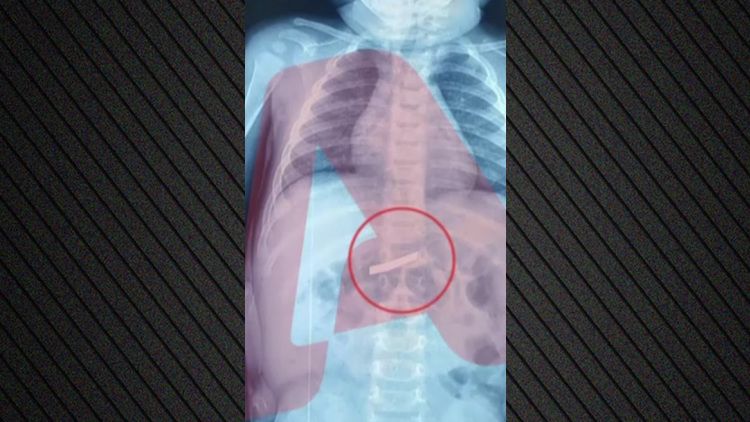

Τυχερός μέσα στην ατυχία του στάθηκε ένας 53χρονος κυνηγός, τον οποίο πέρασε για... αγριογούρουνο ένας 67χρονος φίλος του με τον οποίο είχαν πάει για κυνήγι σε μια αγροτική περιοχή της Άρτας και τον πυροβόλησε τραυματίζοντάς τον, ευτυχώς χωρίς να διατρέχει κίνδυνο η ζωή του!

Το νέο κυνηγετικό ατύχημα που λίγο έλειψε να καταλήξει σε τραγωδία, συνέβη το μεσημέρι της Τετάρτης σε μια δασική περιοχή μεταξύ των κοινοτήτων Φωτεινού και Άνω Πέτρας, όπου η παρέα των κυνηγών είχε στήσει καρτέρι για αγριογούρουνα. Οι δύο άντρες απομακρύνθηκαν κάποια στιγμή αναζητώντας τα ογκώδη θηλαστικά, αλλά ξαφνικά ο 67χρονος είδε κάτι να κουνιόται πίσω από βάτα και πάτησε τη σκανδάλη νομίζοντας πως ήταν αγριόχοιρος.

Ο 53χρονος έπεσε στο έδαφος σφαδάζοντας από τους πόνους και οι φίλοι του που έτρεξαν κοντά του διαπίστωσαν ότι είχε τραυματιστεί στον ώμο και τον θώρακα. Αμέσως τον μετέφεραν στο νοσοκομείο της Άρτας, όμως λόγω της σοβαρότητας της κατάστασής του διακομίστηκε σε νοσοκομείο της Πάτρας όπου νοσηλεύεται εκτός κινδύνου. Οι άνδρες της Ασφάλειας συνέλαβαν τον 67χρονο για πρόκληση επικίνδυνης σωματικής βλάβης από αμέλεια και τον οδήγησαν στον εισαγγελέα Πρωτοδικών Άρτας.